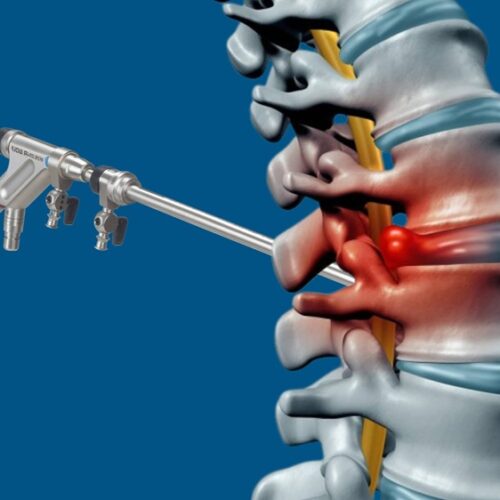

Was bedeutet „endoskopische Lendenwirbelsäulenoperation“?

Antwort: Methoden, die im Alltag als „völlig blutlos“ oder...